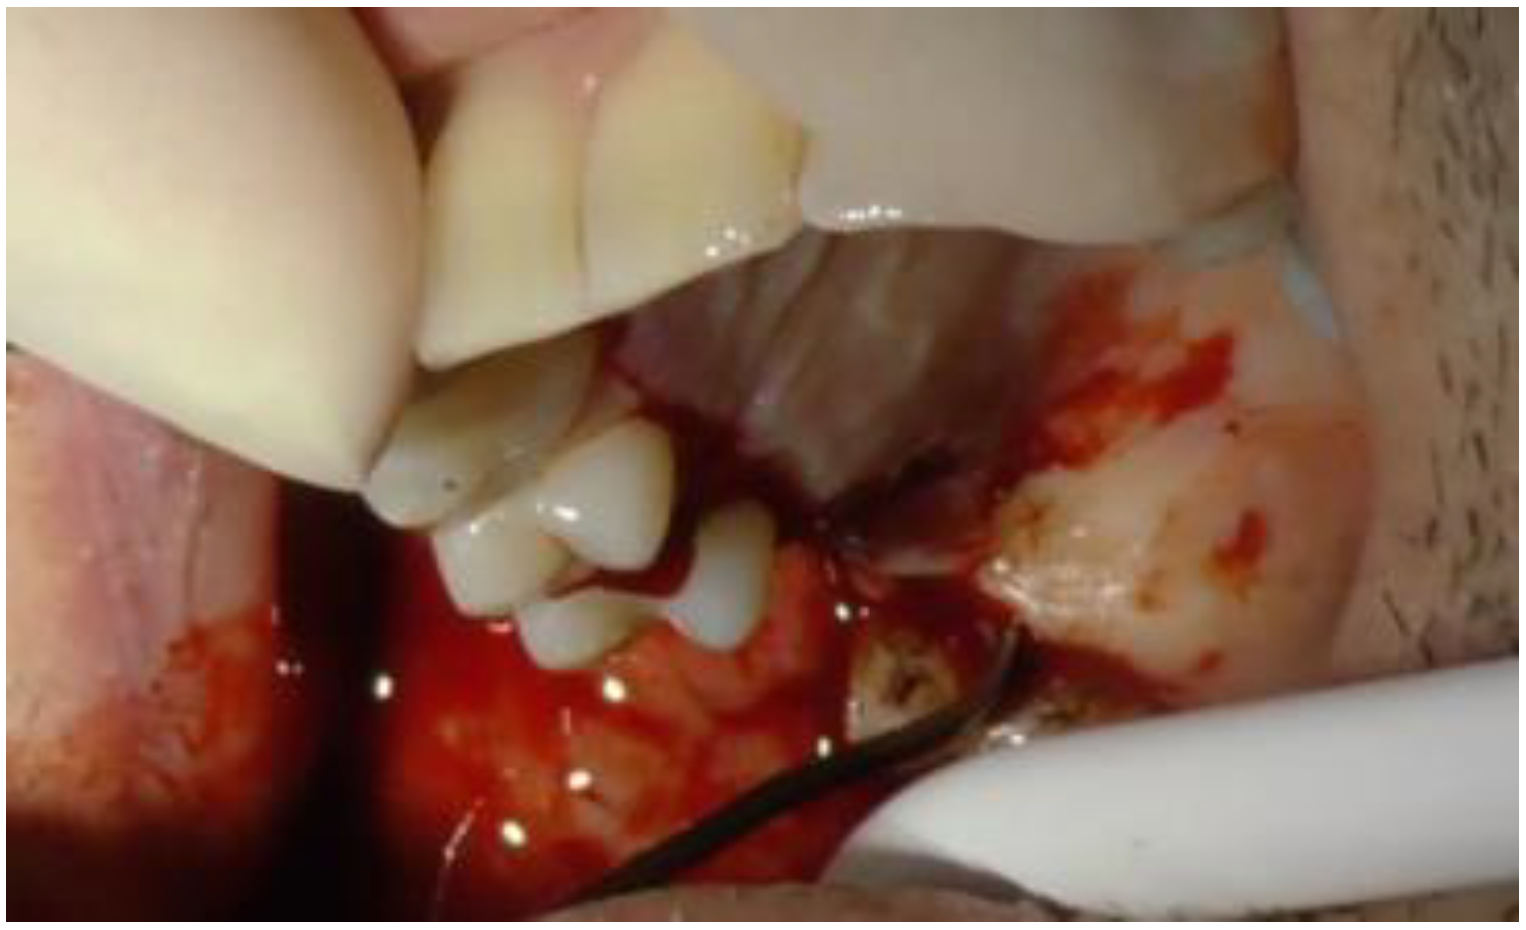

2.1. Clinical and Surgical Procedures